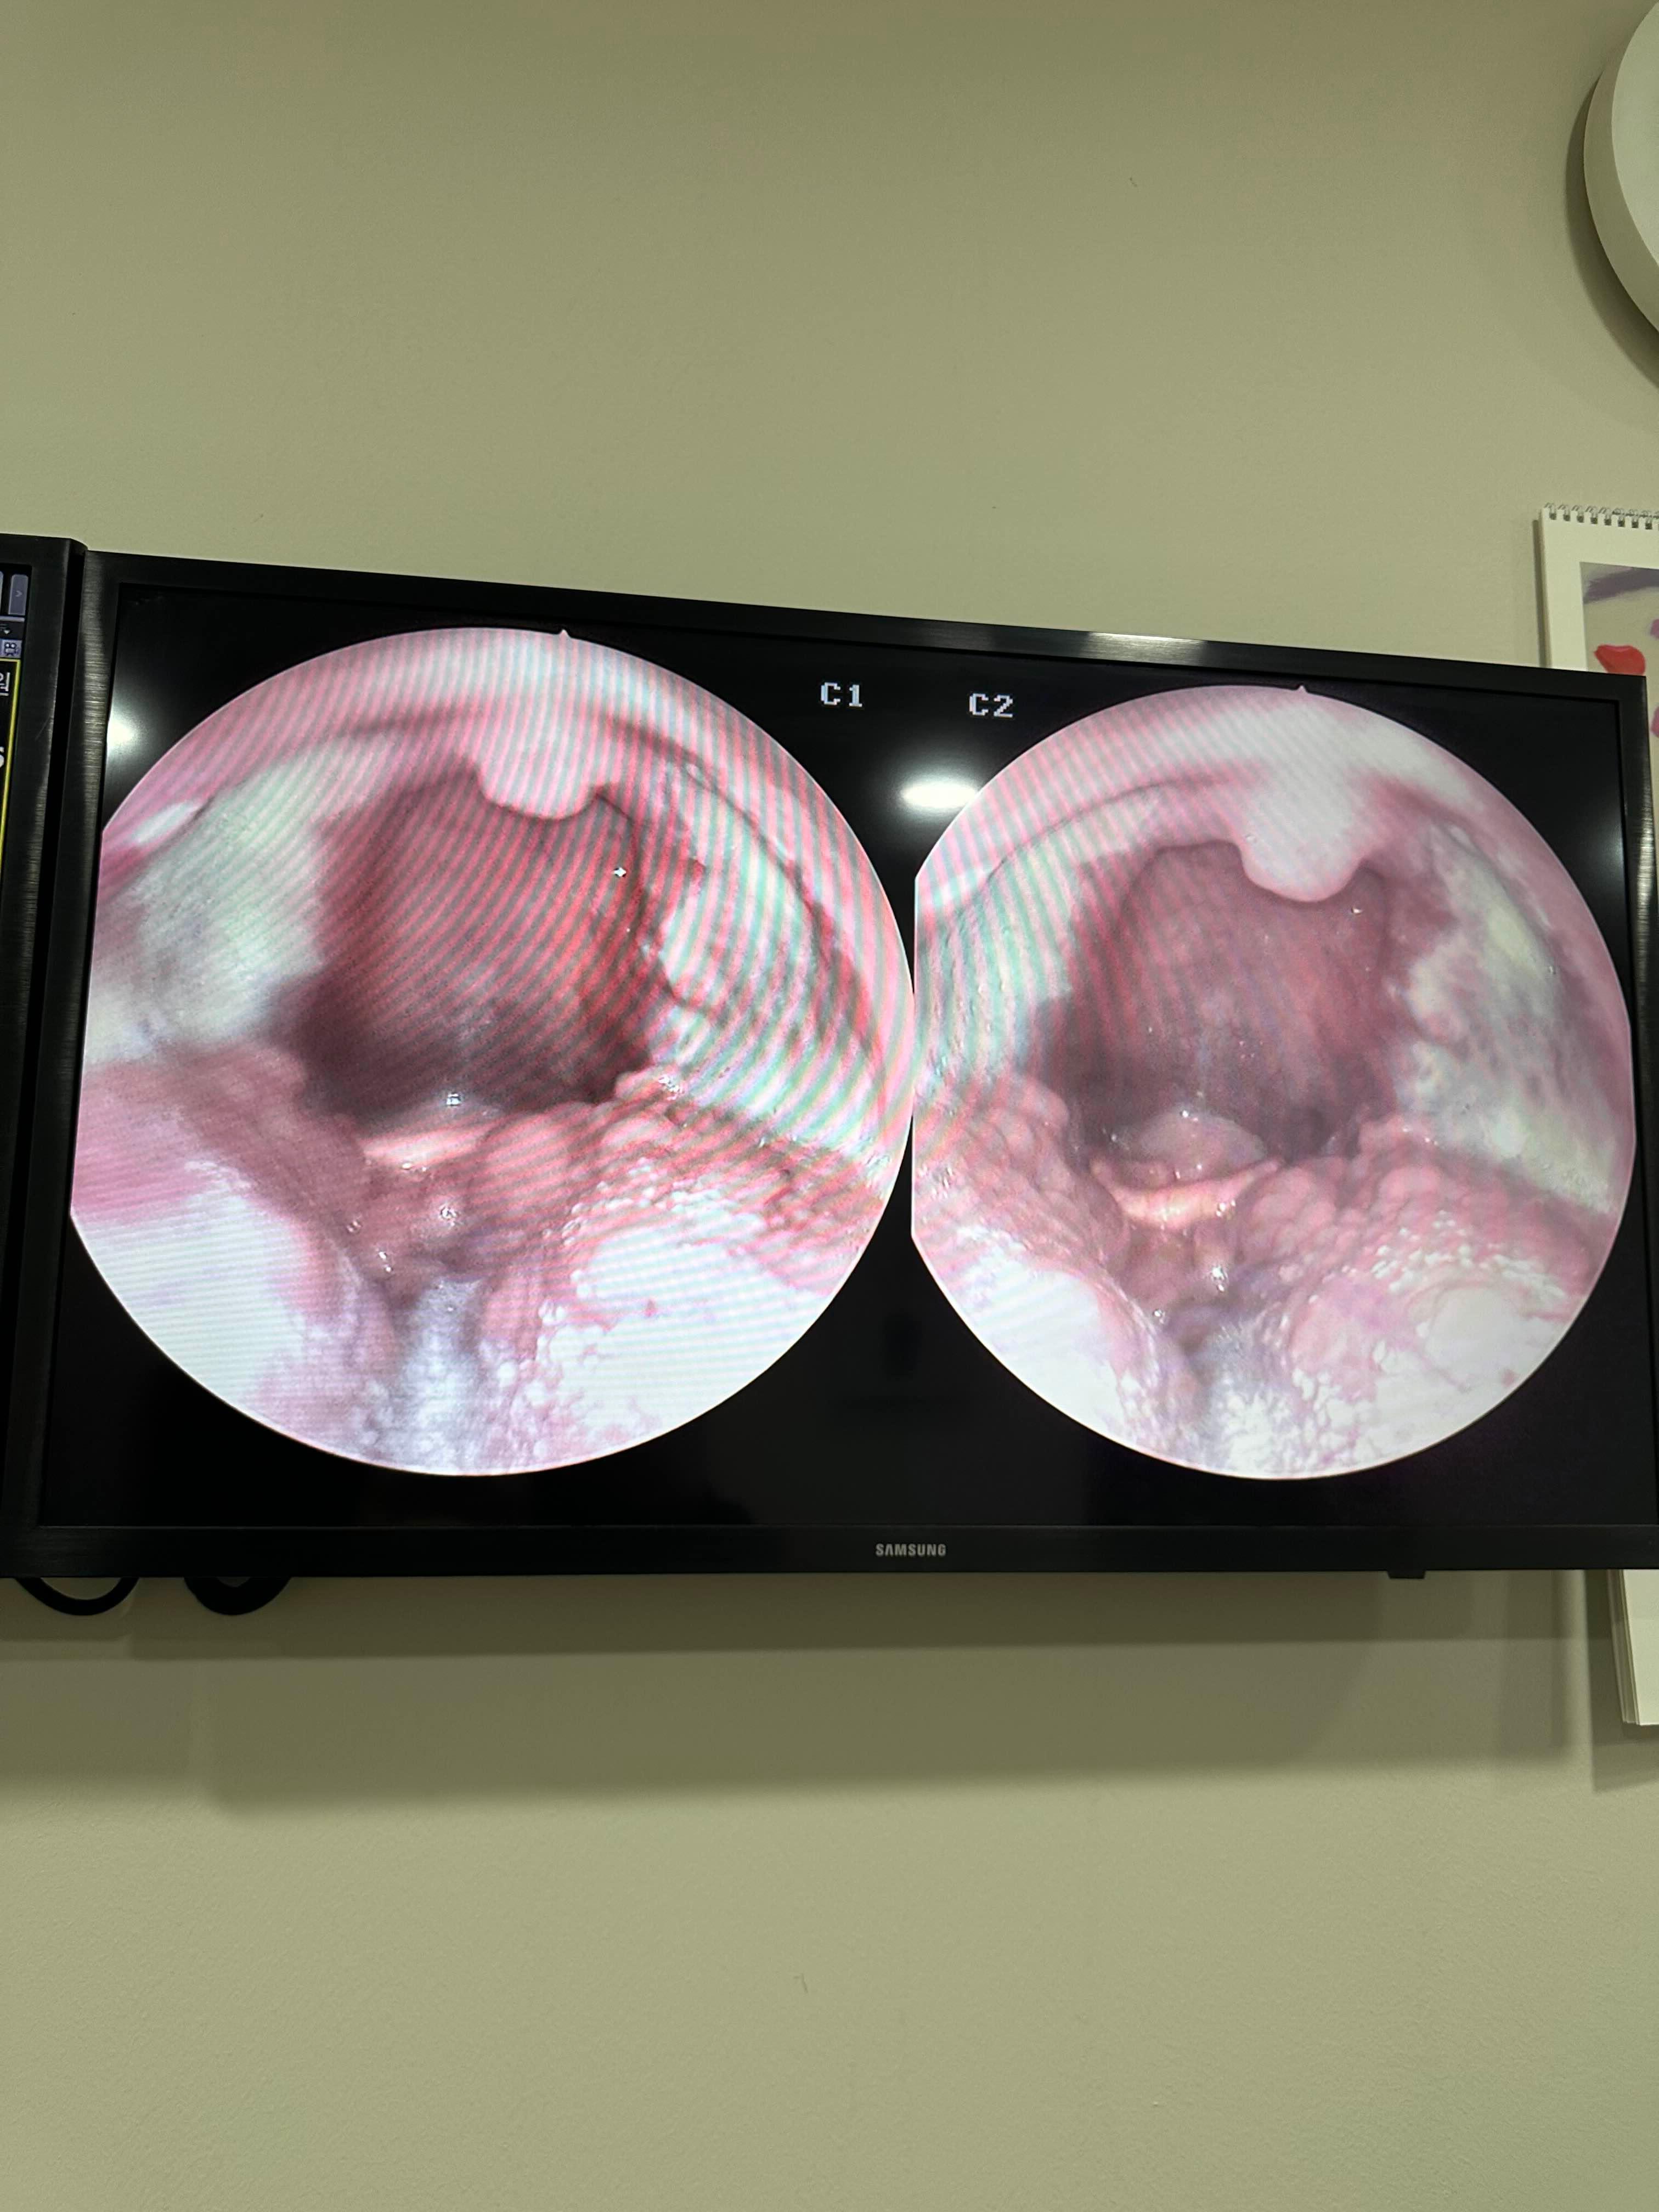

이게 수술후 2주 된 지금.

목이 갈수록 너무 좋아짐.

새살이 잘 차오르고 있다하시고~

먹는것도 이제는 좀더 편히 먹어도 된다는 말을들음.